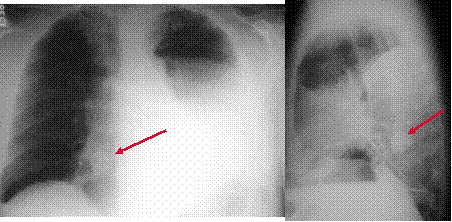

Beware of tunnel vision!